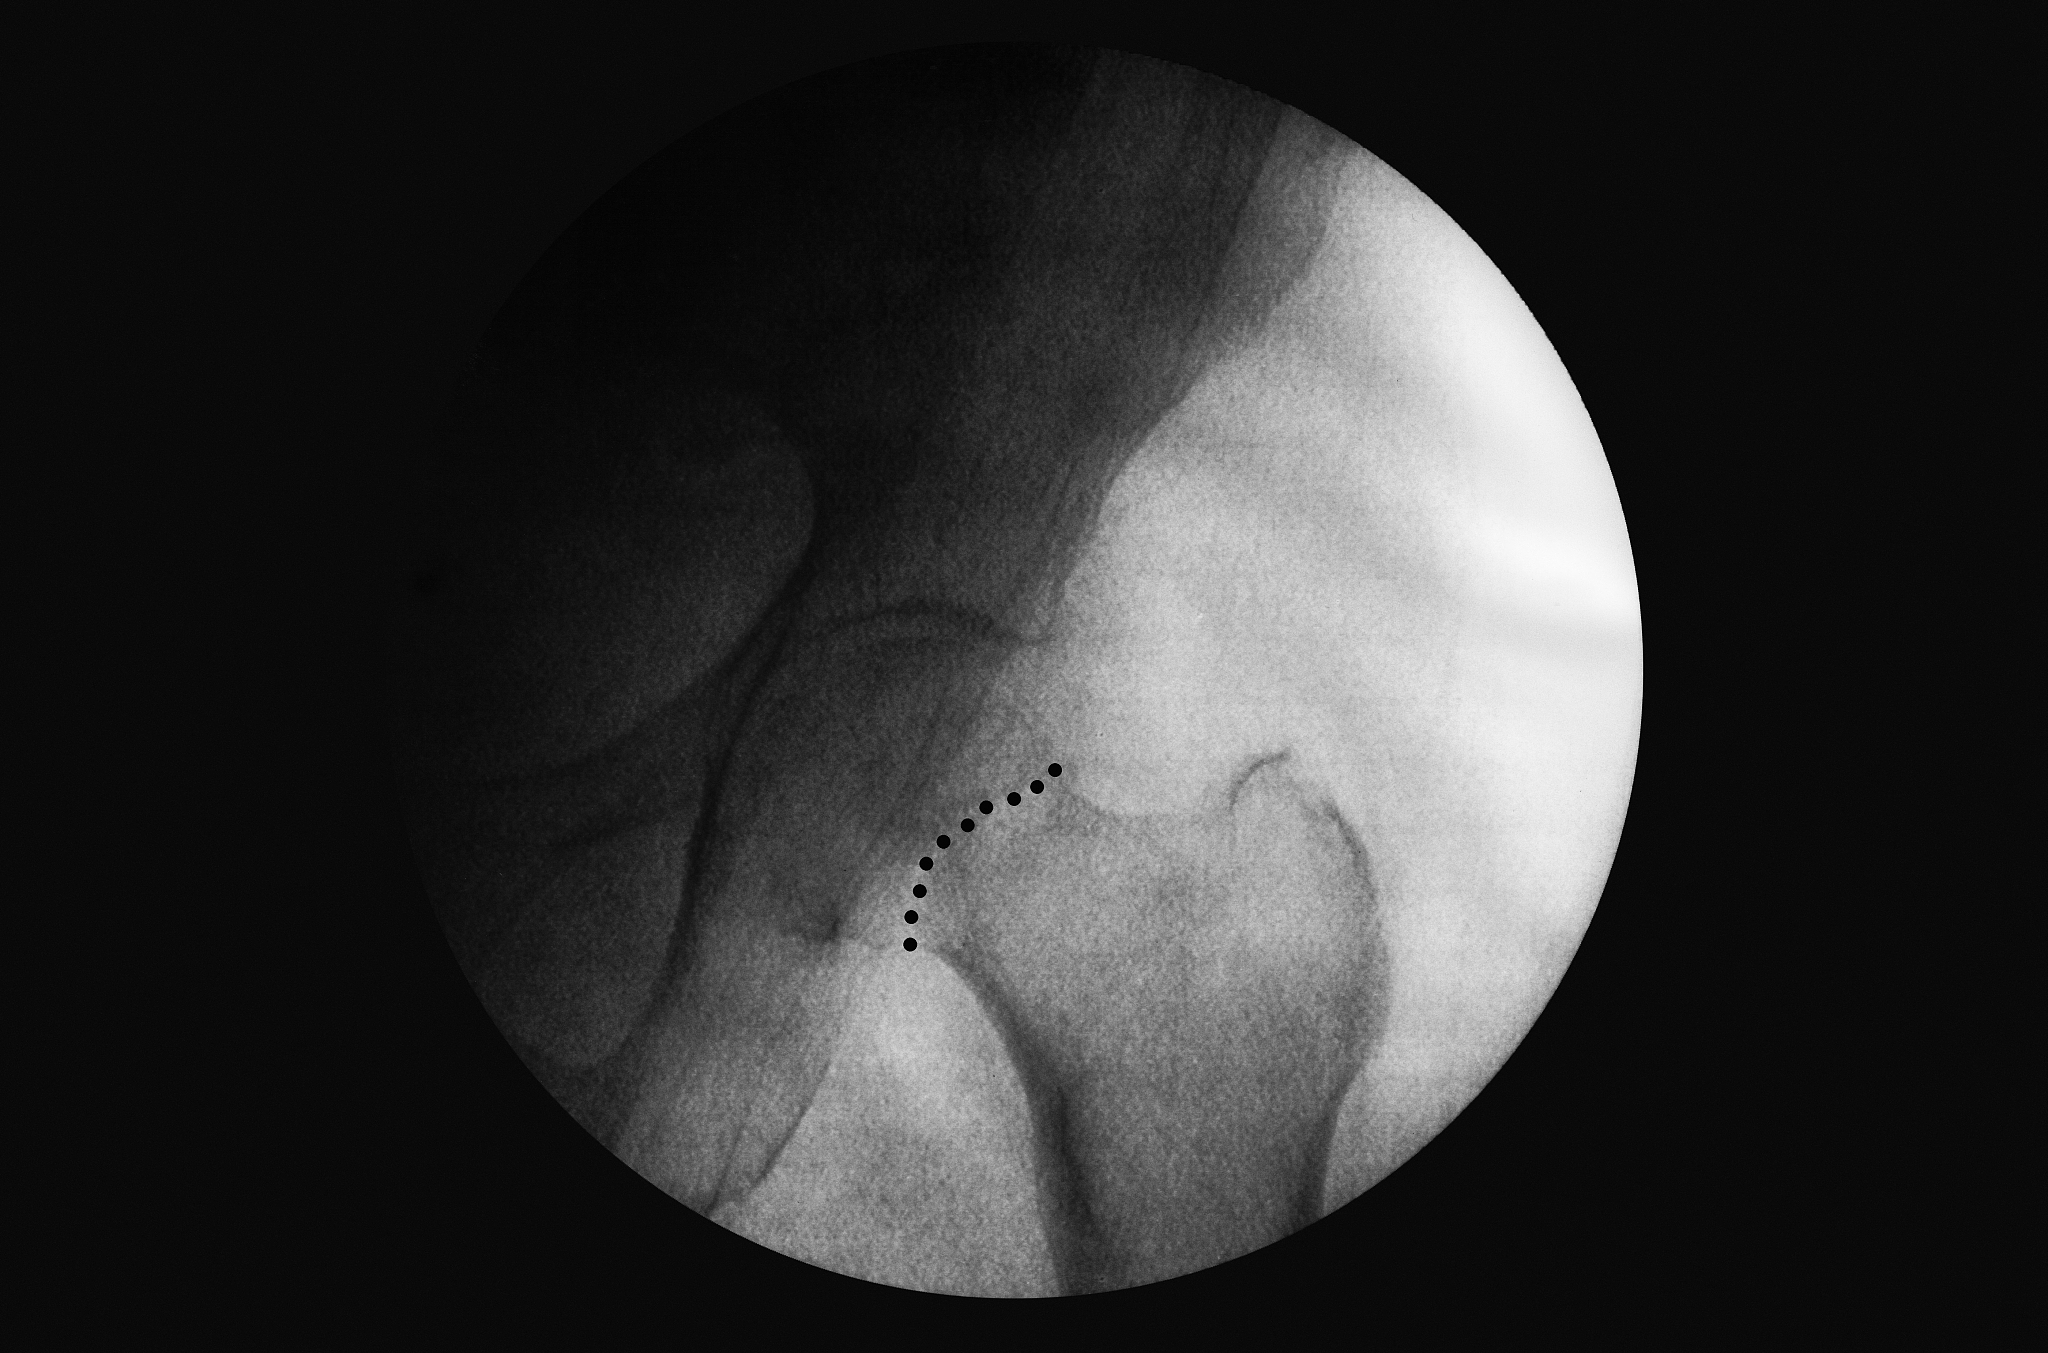

• 脊柱退行性变: 高龄患者常伴有椎间盘突出、椎管狭窄等脊柱退行性变,增加了椎管内穿刺的难度和风险。* 心肺功能下降: 高龄患者心肺功能储备下降,对麻醉药物的代谢和清除能力降低,容易出现麻醉深度过深或过浅,增加术中和术后并发症的风险。